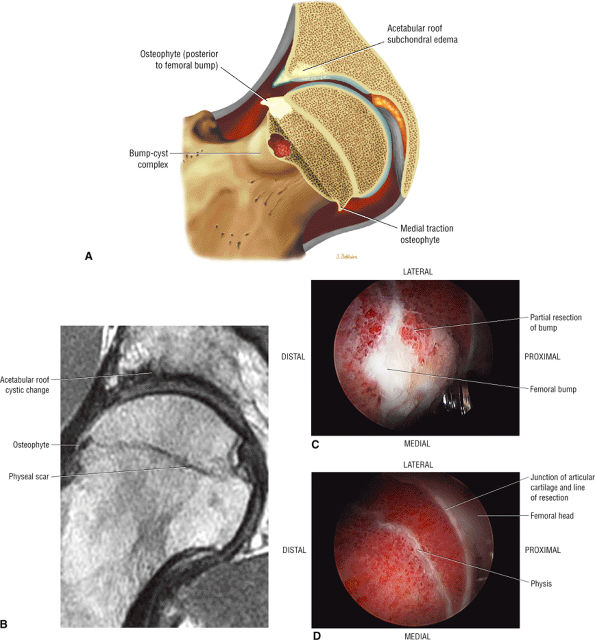

Dysplastic bump in the anterolateral femoral head-neck junction associated with cam-type femoroacetabular impingement

In DDH the labrum may be hypertrophic and associated with a femoral head chondral crease.

An enlarged or hypertrophied labrum may occur in patients with mild DDH.17 We have observed a femoral head chondral crease (Fig. 3.66) in these patients, creating a demarcation trough medial to a femoral head bump immediately proximal to the physeal scar. Patients who demonstrate femoroacetabular impingement (or lateral acetabular rim syndrome in DDH) also have direct impingement between the lateral acetabular labrum and the femoral head.